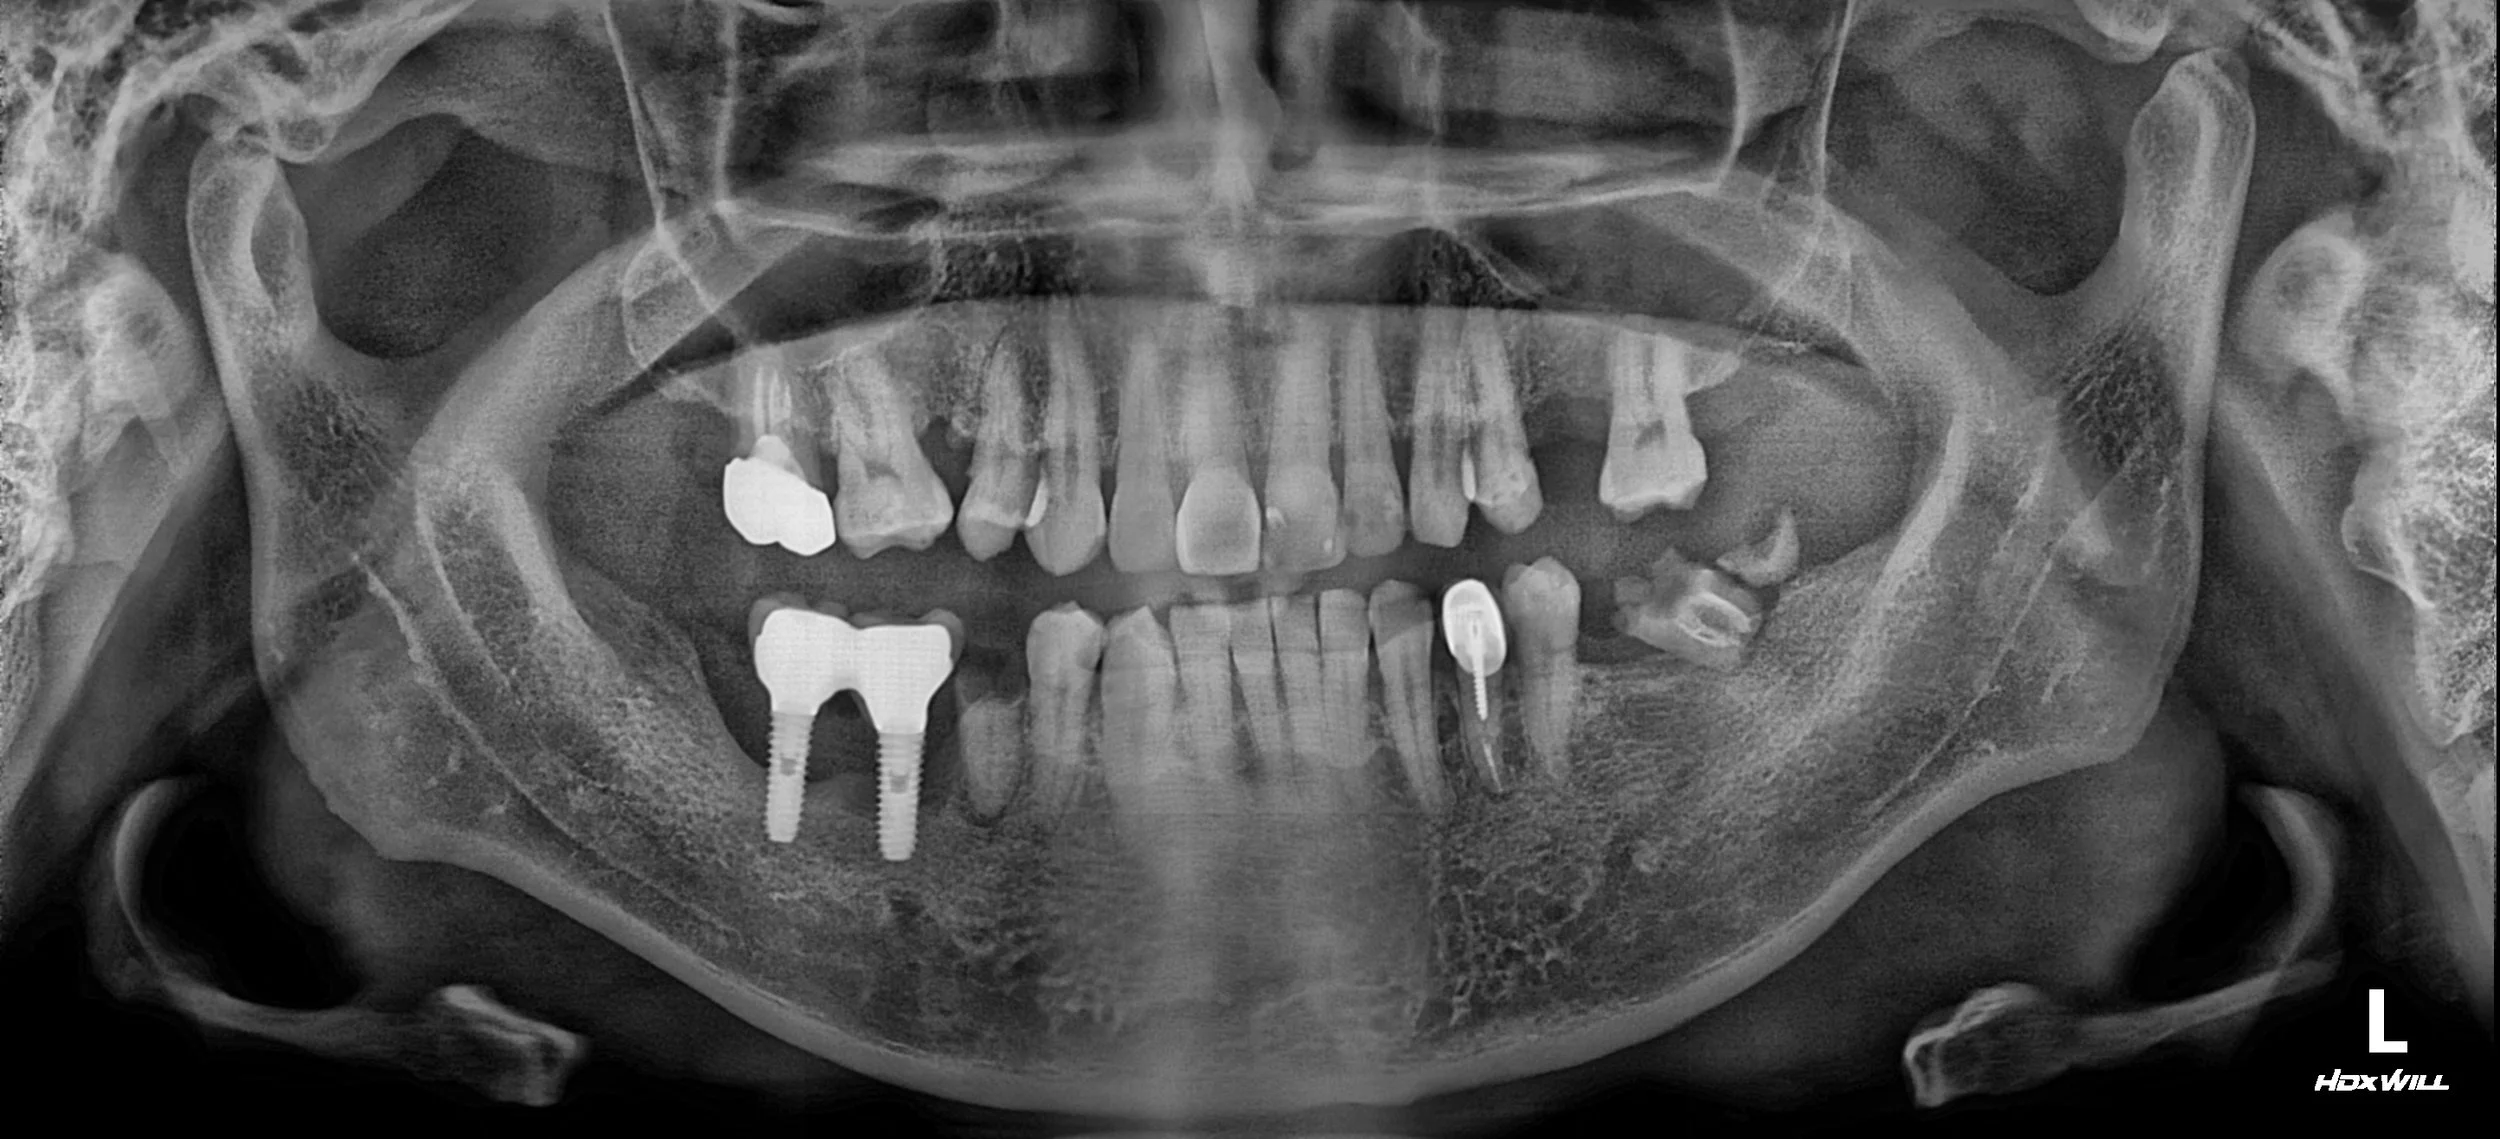

OPG - BEFORE

• Failing and Lost Implants: Previous implants were non-functional or had been removed due to severe peri-implantitis and bone loss.

• Severe Alveolar Resorption: The supportive bone was highly compromised, both horizontally and vertically, particularly in the failing segments.

1. Initial Debridement & Removal: Non-restorable failing implants and hopeless teeth were removed. This phase was crucial for eradicating infection and stabilizing the periodontal foundation.

2. Surgical Phase (Hard & Soft Tissue): Simultaneous or staged Guided Bone Regeneration (GBR) was performed to address severe bone atrophy. Following initial healing, a vestibuloplasty was conducted to deepen the vestibule and improve the soft tissue quality for long-term health.